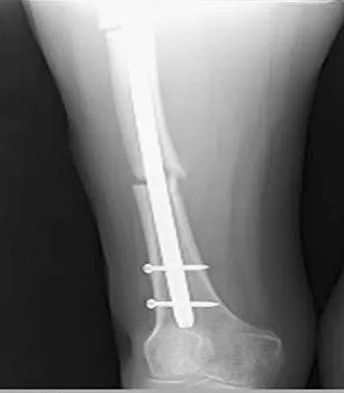

A 24-year-old woman who has hypotension, a head injury, and who experienced a poor response to resuscitation has been taken to the operating room for a splenectomy. Following abdominal surgery she remains unstable with increasing pulmonary respiratory pressures and decreasing oxygen saturation. She has a transverse mid-diaphyseal fracture of the tibia with a 4-cm laceration and soil-contaminated muscle in the wound. Based on these findings, management should consist of

Because the patient is critically ill and requires expeditious care, stabilization of the long bone fracture is required, but definitive care of the fracture should be postponed. The treatment of choice at this time is irrigation with 12 L of saline solution, followed by debridement and nondefinitive stabilization with a simple four-pin external frame to regain axial and rotational alignment. When the patient's condition is more stable, more definitive care can be performed. Bosse MJ, Kellam JF: Orthopaedic management decisions in the multiple trauma patient, in Browner BD, Jupiter JP, Levine AM, Trafton P (eds): Skeletal Trauma, ed 2. Philadelphia, PA, WB Saunders, 1998, pp 151-164. Weresh MJ, Stover MD, Bosse MJ, Jeray K, Kellam JF: Pulmonary gas exchange during intramedullary fixation of femoral shaft fractures. J Trauma 1999;46:863-868.